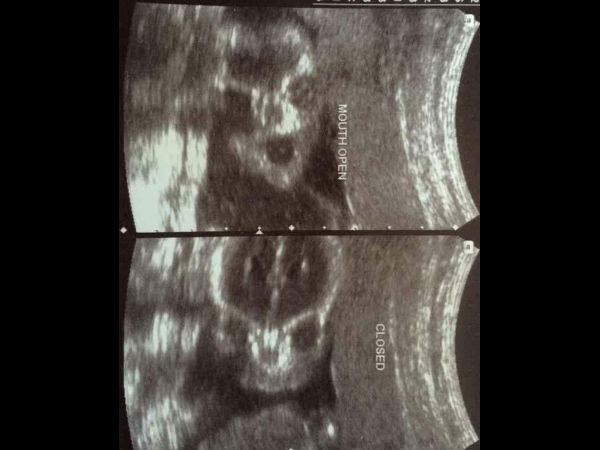

ಚಿತ್ರ#4 ಚಿತ್ರಕ್ಕೆ ಭಂಗಿ ನೀಡುತ್ತಿದೆಯೇ?

ಚಿತ್ರ ತೆಗೆಯುವವರು ಬಂದಾಗ ಎಲ್ಲರೂ ಇದಕ್ಕೆ ಸೂಕ್ತ ಭಂಗಿ ನೀಡಲು ಕೊಂಚ ಮುಗುಳ್ನಗುತ್ತಾರಲ್ಲಾ, ಈ ಕಲೆಯನ್ನು ಈ ಮಗು ಗರ್ಭದಲ್ಲಿಯೇ ಕಲಿತು ಕೊಂಡಂತಿದೆ. ಈ ಚಿತ್ರದಲ್ಲಿ ಬಾಯಿಯನ್ನು ಪೂರ್ಣವಾಗಿ ತೆರೆದು ಚಿತ್ರಕ್ಕೆ ಭಂಗಿ ನೀಡುವಂತೆ ಕಾಣುತ್ತಿದೆ. ಈ ಮಗುವಿನ ಚಿತ್ರ ತೆಗೆದಾದ ಬಳಿಕ ಬಾಯಿ ಮುಚ್ಚಿದ್ದರಿಂದ ಇನ್ನೊಂದು ಚಿತ್ರದಲ್ಲಿ ಹಾಗೇ ಮೂಡಿಬಂದಿದೆ.